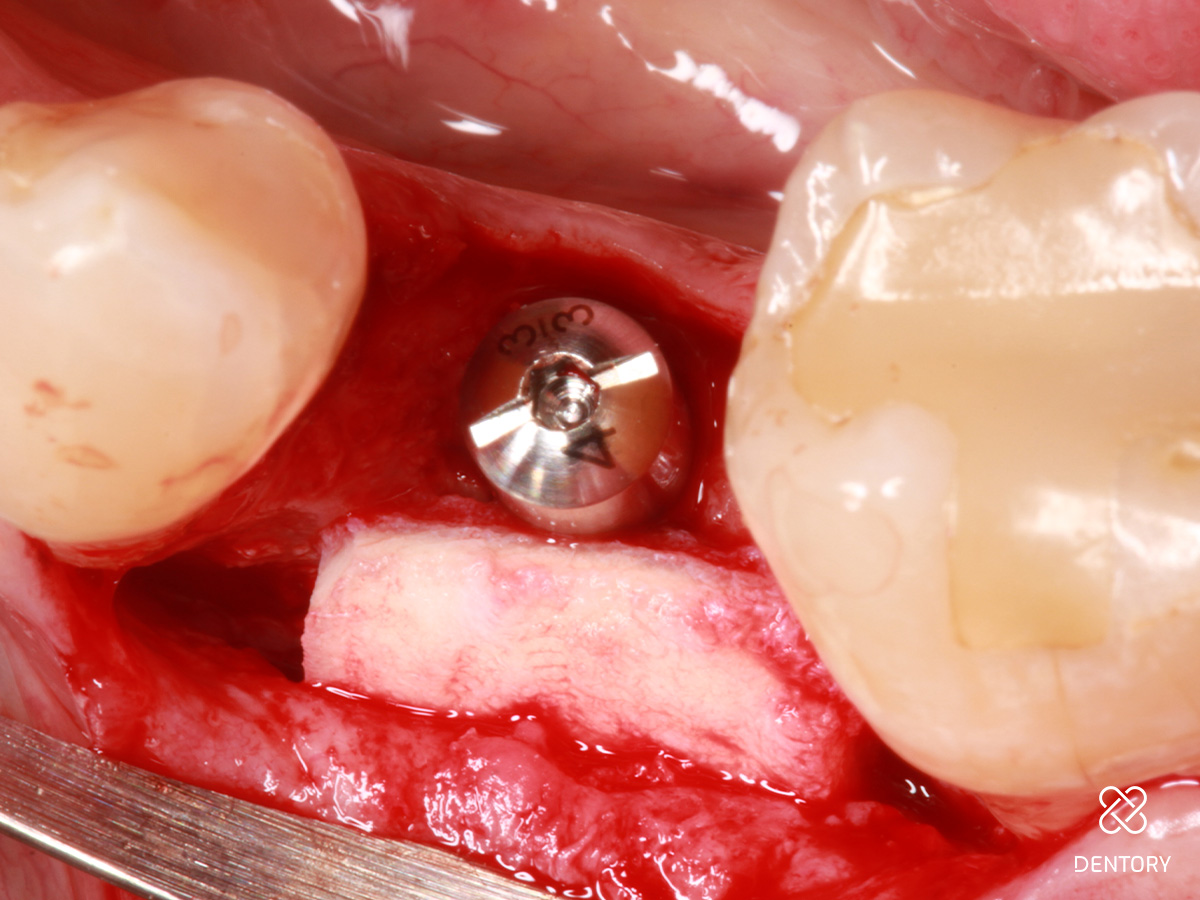

Abbildung 11

Gute Defektauffüllung mit minimalem Restdefekt von < 0,5 mm auf der bukkalen Seite.